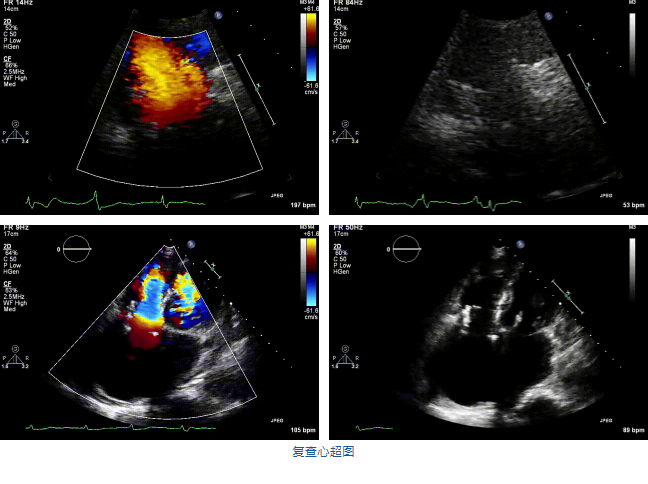

2021年12月7日,復(fù)旦大學(xué)附屬中山醫(yī)院葛均波院士團(tuán)隊(duì)完成的首批兩例LuX-Valve Plus經(jīng)血管三尖瓣置換患者順利出院,從患者入院至出院僅歷時(shí)一周時(shí)間,出院時(shí)患者狀態(tài)恢復(fù)良好,復(fù)查心超三尖瓣無反流。

兩例患者是都是外科手術(shù)高危的極重度三尖瓣反流的老年女性,反復(fù)下肢水腫、腹脹、納差,活動(dòng)耐力減退。一例患者風(fēng)濕性心臟病,二尖瓣生物瓣置換術(shù)后,房顫,心超顯示三尖瓣極重度反流(最大反流寬度15mm);另一例患者房顫,心超示三尖瓣極重度反流(最大反流寬度23mm)。

結(jié)合術(shù)前CT評估結(jié)果,葛均波院士團(tuán)隊(duì)最終決定選用LuX-Valve Plus 50mm和55mm兩種型號(hào)的瓣膜,并于2021年11月30日順利完成LuX-Valve Plus經(jīng)血管三尖瓣置換術(shù),手術(shù)室即刻拔除氣管插管,術(shù)后第二天轉(zhuǎn)出心內(nèi)科監(jiān)護(hù)室,下床活動(dòng)。術(shù)后患者三尖瓣反流癥狀得到顯著改善,復(fù)查心超結(jié)果顯示人工三尖瓣瓣膜支架固定穩(wěn)定,瓣葉關(guān)閉形態(tài)未見異常,未見明顯反流。